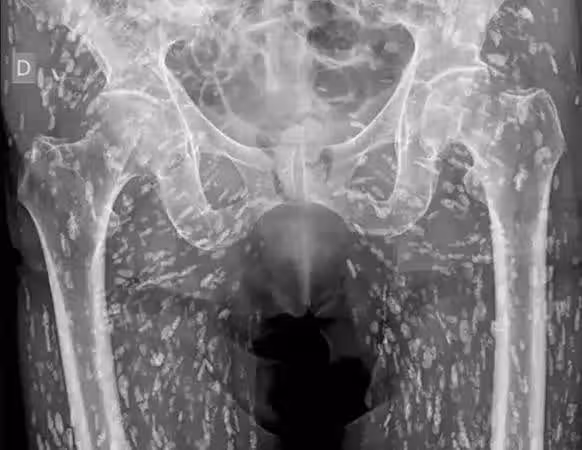

▲國外一名男子因食用未煮熟的豬肉,染上豬囊尾蚴病,骨盆布滿了密密麻麻的蟲卵。(圖/翻攝自X)

國外一名男子因臀部疼痛前往醫院檢查,不料X光片竟顯示,他的骨盆周圍布滿了數以百計的蟲卵,被斷定患上由豬肉絛蟲(Taenia solium)引起的豬囊尾蚴病(Cysticercosis) ,而這種疾病是因為男子食用未煮熟或生豬肉所致。